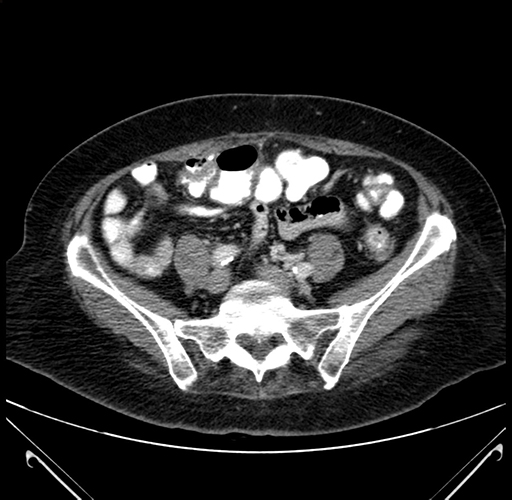

Pre-Chemo: Axial Venous

Axial Venous